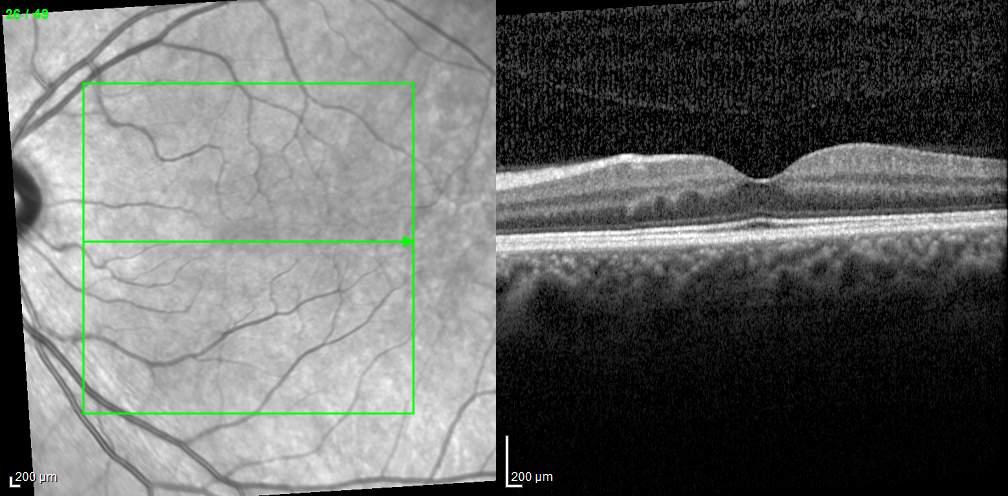

MNV may also develop in patients with central serous chorioretinopathy. In this condition, the pathogenesis of MNV is not yet fully understood. It is known that it can occur after laser photocoagulation or photodynamic therapy as a compensatory response to treatment; however, MNV may also develop in cases without history of laser treatment. In these cases, MNV may develop in a manner similar to AMD, where the rupture of Bruch’s membrane due to chronic RPE changes and long-standing serous pigment epithelium detachment allows for the growth of Type 1 neovascularization.33–36 (Figure 6)

Figure 6. Multimodal imaging of Type 1 macular neovascularization secondary to central serous chorioretinopathy. Fluorescein angiography (A and B) showing pinpoints of hyperfluorescence with leakage in the late phase. Indocyanine green angiography (C and D) displaying the central hyperfluorescent area and the adiacent area of choridal hyperpermeability. Fundus autofluorescence (E) revealing abnormalities of retinal pigment epithelium. The en face of optical coherence tomography angiography (F) showing the neovascular network and the B-scan displaying the shallow irregular retinal pigment epithelium elevation with subretinal fluid (G).